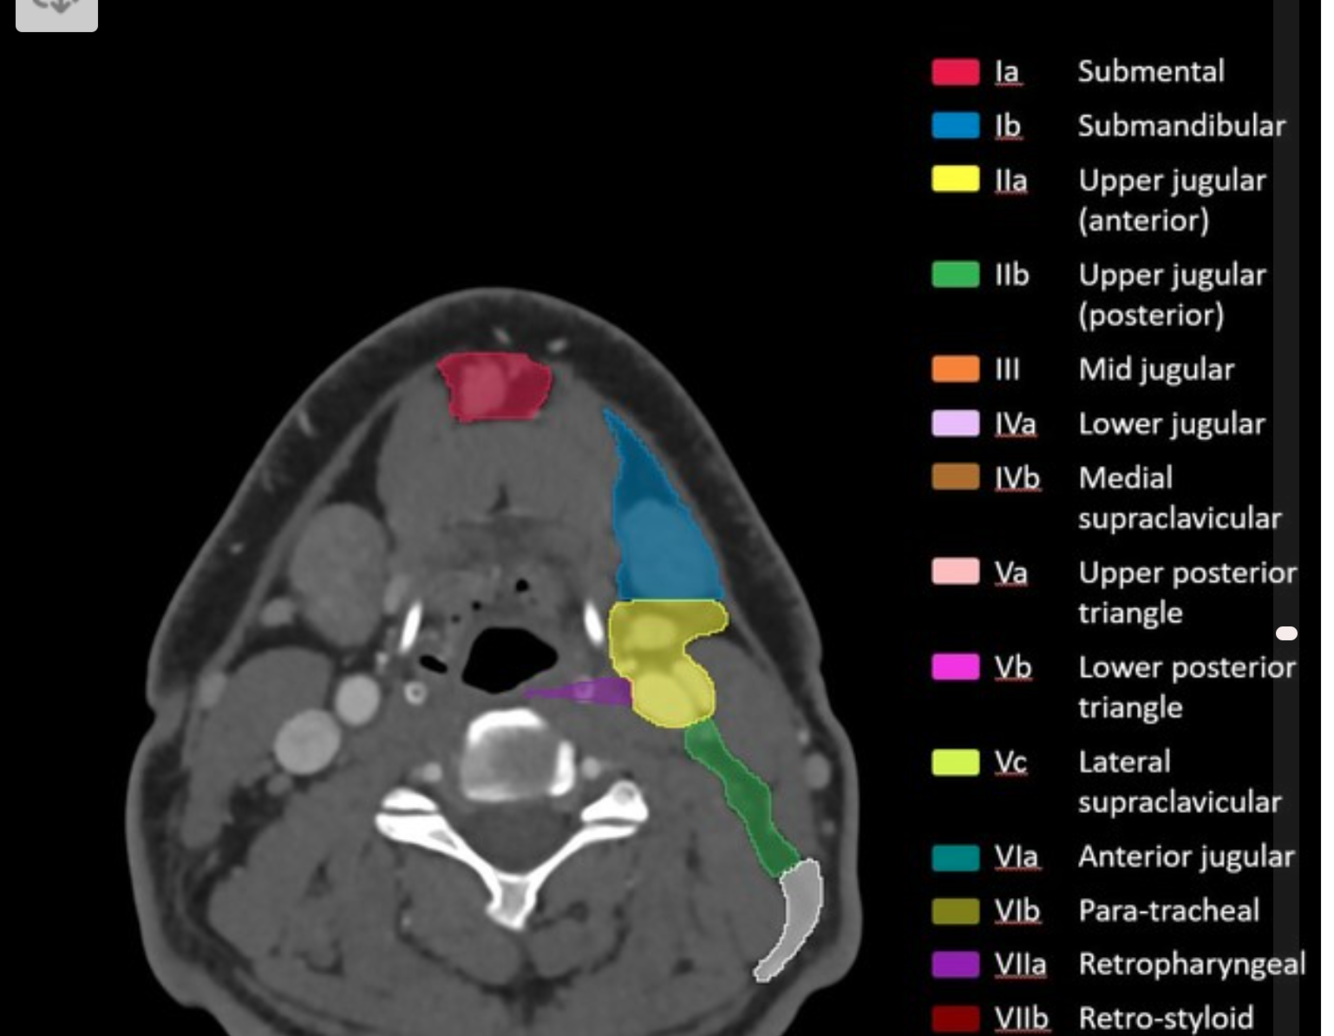

Lymph node level 1a

superiorly:

inferiorly:

anteriorly:

posteriorly:

There are two sublevels:

Submental LNs

superiorly: mylohyoid muscle and mandible

inferiorly: inferior border of the hyoid bone

anteriorly: platysma muscle

posteriorly: posterior border of the submandibular gland

level Ia (submental nodes): anteromedial between the anterior bellies of both digastric muscles

level Ib (submandibular nodes): posterolateral to the anterior belly of the digastric muscles

Level II lymph nodes

Boundaries

posterolaterally:

medially:

Level II: upper internal jugular (deep cervical) chain

superiorly: base of the skull at the jugular fossa

anteriorly: posterior border of the submandibular gland

posterolaterally: posterior border of the sternocleidomastoid muscle

medially: medial border of the internal carotid artery

level IIa: inseparable from or anterior to the posterior edge of the internal jugular vein; includes jugulodigastric nodal group

level IIb: posterior to and separable by a fat plane from the internal jugular vein

Level IV: lower internal jugular (deep cervical) chain

superiorly: inferior border of the cricoid cartilage

inferiorly: level of the clavicle/manubrium

anteriorly: anterior border of the sternocleidomastoid muscle

posterolaterally: oblique line drawn through the posterolateral edge of the sternocleidomastoid muscle and the lateral edge of the anterior scalene muscle 2

medially: medial border of the common carotid artery

includes medial supraclavicular nodes including Virchow node 1

Level V: posterior triangle

superiorly: skull base at the apex of the convergence of sternocleidomastoid and trapezius muscles

inferiorly: level of the clavicle

anteromedially: posterior border of the sternocleidomastoid muscle

posterolaterally: anterior border of the trapezius muscle

level Va: superior half, superior to inferior border of the cricoid cartilage (posterior to levels II and III); includes spinal accessory nodes

level Vb: inferior half, inferior to inferior border of the cricoid cartilage (posterior to level IV); includes lateral supraclavicular nodes 1

Level VI: central (anterior) compartment

superiorly: inferior border of hyoid bone

inferiorly: superior border of manubrium (suprasternal notch)

anteriorly: platysma muscle 8

posteriorly: trachea (medially) and prevertebral space (laterally) 8

laterally: medial borders of both common carotid arteries (medial to levels III and IV)

includes anterior jugular, pretracheal, paratracheal, prelaryngeal/precricoid (Delphian), and perithyroidal nodes